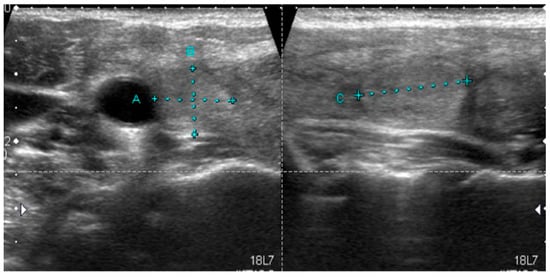

RAS mutations are typical for follicular tumors (including adenomas and carcinomas), but they also occur in the follicular variant (FV) of PTC. The follicular variant is the second most common type of PTC after the classic variant [,]. Nuclear features are typical for PTC, but the growth pattern is follicular. Based on the molecular alterations and biological behavior, FV tumors were divided into two main subtypes of FV PTC: Infiltrative and encapsulated with invasion []. As it has already been mentioned, the lesions previously classified as the follicular variant of PTC (including EFVPTC) now include only those lesions with angiolymphatic or capsular invasion, or a wandering/infiltrative border. Well-demarcated or encapsulated lesions without invasion belong to the newly described entity NIFTP []. NIFTP is a tumor with a very good prognosis and rather benign behavior. The extent of surgical procedures can be limited in this case, although surgery is required. NIFTPs usually harbor activating RAS mutation (30–59%), including N-RAS, H-RAS, and, less commonly, K-RAS mutations [,,,,,]. A lack of BRAFV600E mutation, detected by molecular assays or immunohistochemistry, and lack of BRAFV600E-like mutations or other high-risk mutations (TERT, TP53) were included into the 2018 revised diagnostic criteria for NIFTP as secondary criteria []. Rosario and Mourão [] analyzed a series of papers that reported the presence of BRAFV600E in NIFTP and demonstrated that, initially, the tumors were probably inappropriately classified as NIFTP, but in a further assessment, the presence of papillae and/or even capsular invasion was observed. BRAFK601E mutation was found in a subset of NIFTP cases (4%) [,], but this group may require a similar reassessment. Although NIFTPs predominantly bear RAS mutations, tumors with other genetic alterations, such as PPARγ and THADA mutations, were also described [,]. NIFTP tumors did not present malignant US features. They are frequently isoechoic or even hyperechoic, with well-defined margins and no microcalcifications [,,]. Rosario et al. [] demonstrated that sonographic images of NIFTP thyroid nodules were classified according to ACR as TIRADS 5 only in 3.5%. More frequently, they corresponded to TIRADS 4 (67.8%) or TIRADS 3 (28.5%) []. Similarly, only a small percentage of NIFTP lesions were classified as ATA high-risk lesions while 66% of them corresponded to the low-risk category []. A typical sonographic pattern of NIFTP is presented in Figure 3.

Figure 3.

Typical sonographic pattern of RAS-positive NIFTP, normoechoic lesion with well-defined margins and without calcifications.